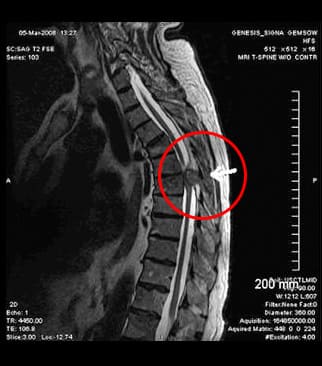

The ECG showed that my heart was fine. I got a full examination at the hospital and found out I had a thoracic osteochondrosis. I didn't expect that! I do sports, go to yoga, sleep on an orthopaedic mattress. All in vain…